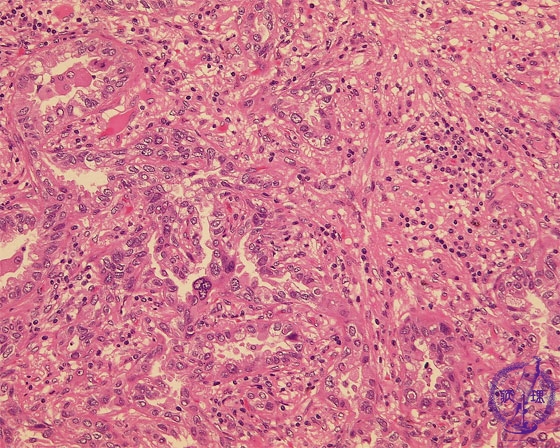

非小細胞肺癌(腺癌)ミクロ像(HE強拡大)

ミクロ像(HE強拡大):腫瘍中心部、浸潤癌の部分では腫瘍細胞は不規則な腺腔を形成しながら浸潤性に増殖している。複雑に入り組んだ間質(星印)にはリンパ球を中心とした炎症細胞の浸潤が見られる。